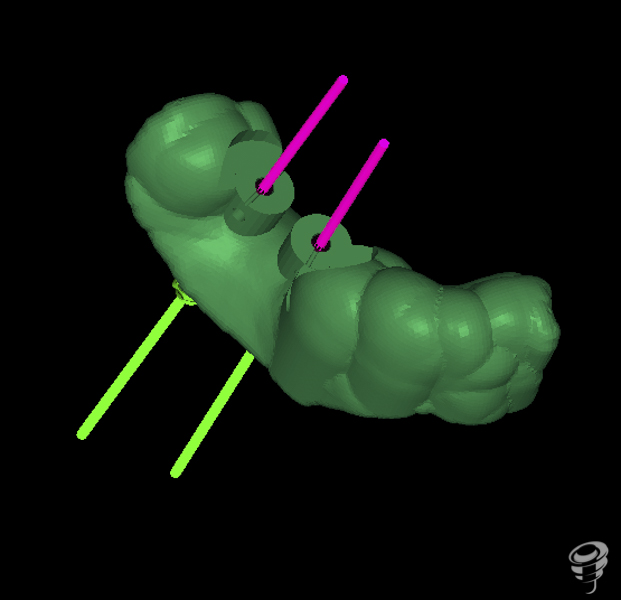

La cirugía guiada permite la planificación de implantes virtuales en el conjunto de datos aportados por la exploraciones tridimensionales del Tac, permitiendo una predeterminación exacta del tratamiento y la transferencia de la planificación de la rehabilitación al campo operatorio.

A.M.R Paciente de 40 años de edad, de sexo femenino, edéntula parcial, no fumadora y sin antecedentes médicos de interés. La paciente fue evaluada radiológicamente con una tomografía computarizada de haz cónico y se procedió a la planificación de su caso mediante el sistema informático Galimplant 3D Exacto®. Se planificaron dos implantes galimplant de 4X10mm (IPX 4010).

Una vez realizada la planificación de los dos implantes, se lleva a cabo la impresión de la férula quirúrgica dento-soportada con dos orificios cilíndricos adaptados a la fresa pin de 2 milímetros de diámetro. Esta fresa tiene la función de guiar tridimensionalmente la posición del implante.